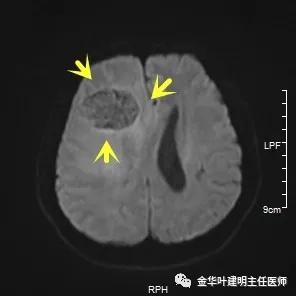

患者某A,今年才45岁,是家里的顶梁柱,于今年8月底检查发现右下肺占位入住本院。住院后查头颅MRI示:右侧额叶占位,结合病史首先考虑转移瘤。肺部病灶经穿刺活检明确是“浸润性腺癌”。我们先来看其肺部病灶:

以上图示术前头颅MRI的图像,病灶明显,伴周围显著水肿,中线结构移位。基本可认为是肺癌伴脑转移。那么怎么治疗呢?需不需要手术?能不能手术?手术怎么做?先开颅还是先开肺?